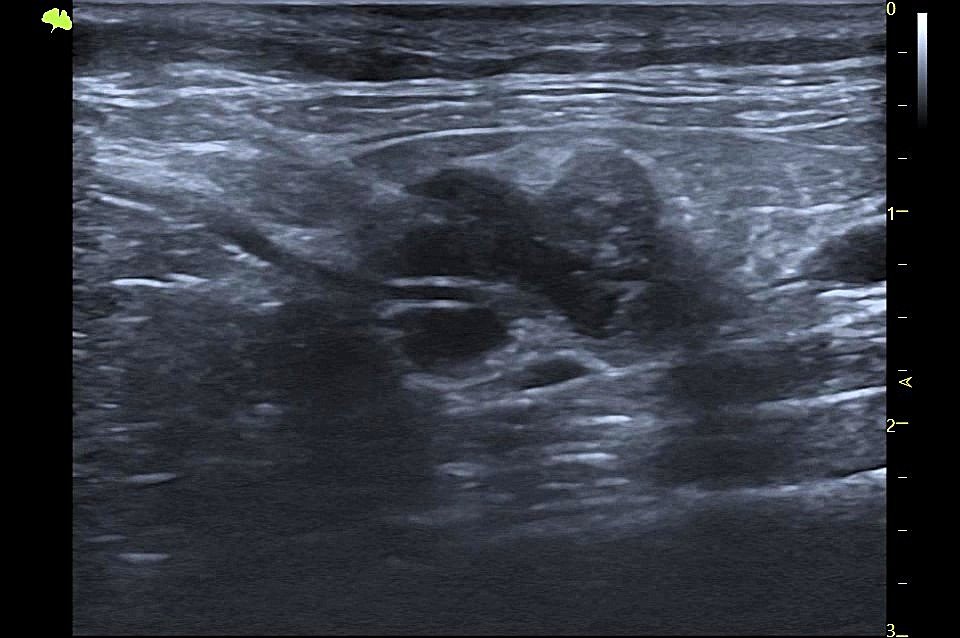

Badanie USG przeprowadziła lek.wet. Monika Morawska z MOONVET Aparat: VINNO G65VET Pacjent: 9-letnia, kastrowana kotka, u której wcześniej wykonano amputację kończyny miednicznej z powodu rozrostu w okolicy stawu skokowego. Histopatologia guza wskazała na mięsaka —złośliwy nowotwór pochodzenia mezenchymalnego. Podczas badania stwierdzono powiększenie prawego węzła chłonnego biodrowego pośrodkowego oraz węzła pachwinowego. Pobrany materiał z węzła biodrowego […]